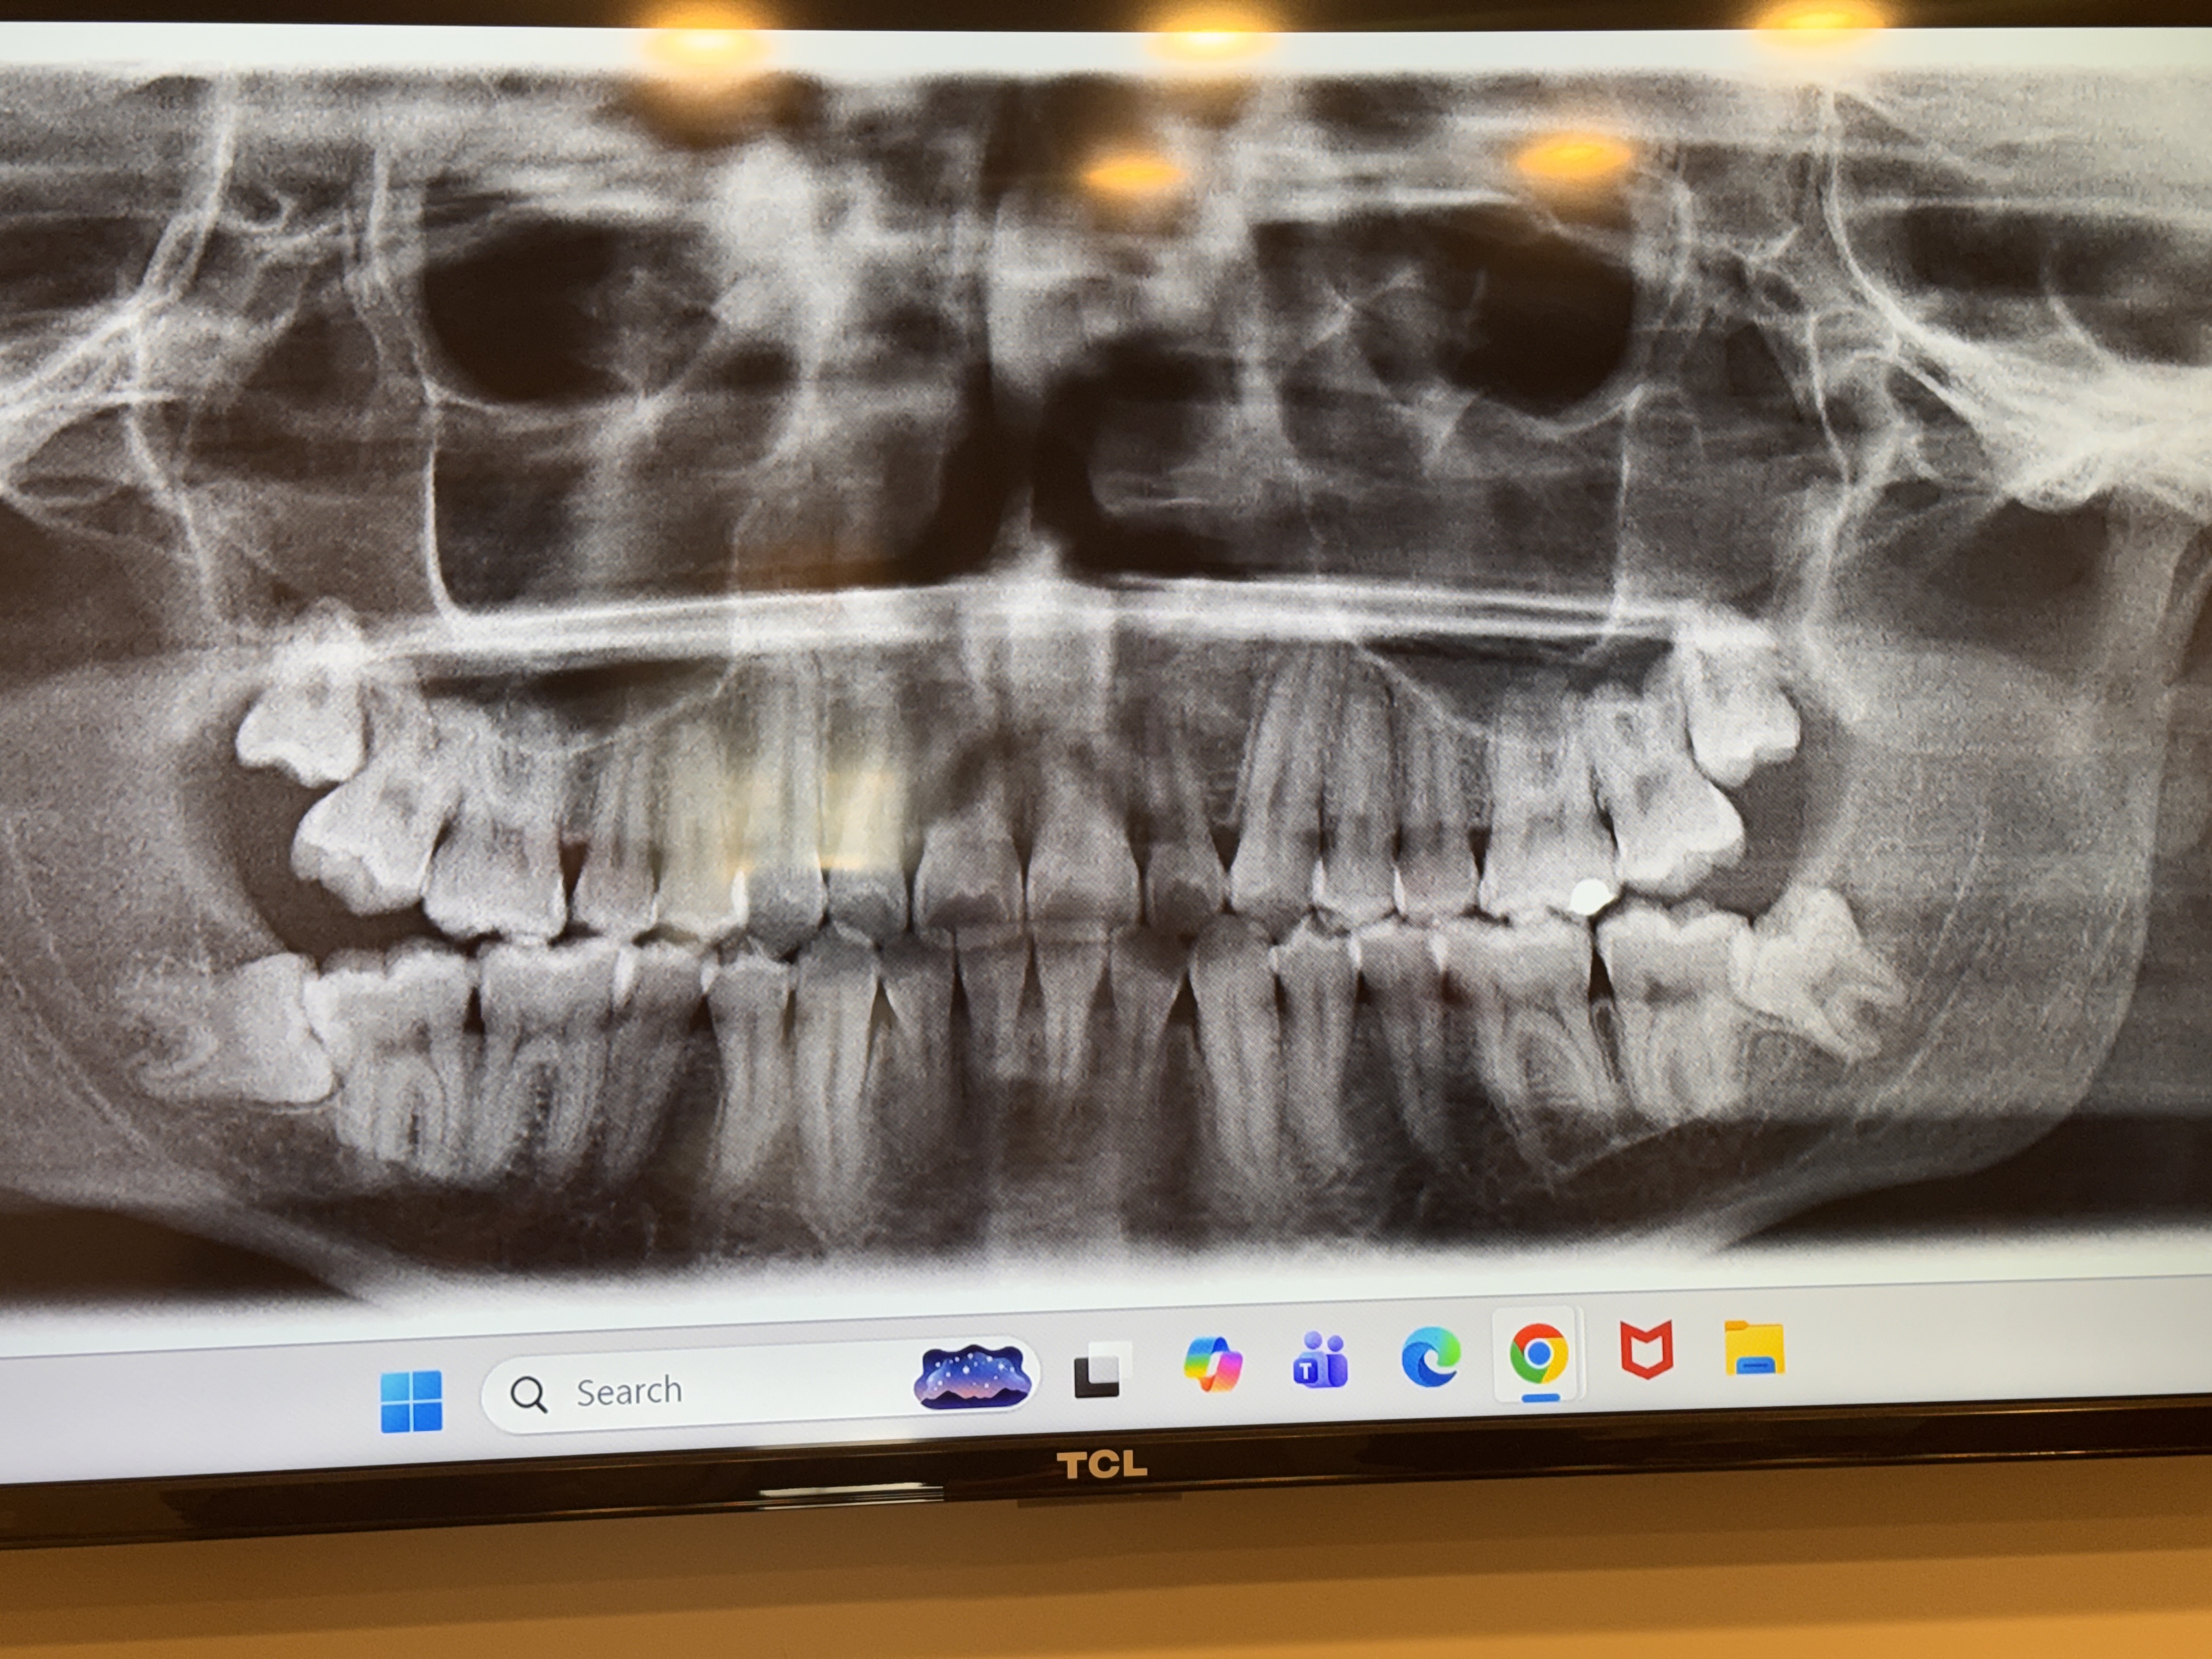

pointless thread since if they are impacted you will have to get them removed unless you want to experience horrible health issues over a negligible amount of jaw widthView attachment 4709932Hello all my fellow gays. I have a real question about my wisdom teeth. I am 19, and my wisdom teeth seem really messed up, but it seems like wisdom teeth removal can lead to resorption and the shrinking of the jaw. My jaw is already not the strongest, and I would not want it to get any worse. The wisdom teeth could also be causing or atleast worsening my uneven jaw, as one side is much more affected. Please let me know what you think, I will have attached the xray of my teeth. They seemed to mostly be suggesting me to get my bottoms removed, but the top ones don’t seem that great either.

My head is gonna turn into a pea brobrother, remove them atleast the one in the bottom, there wont be any bones resemption, but if you keep them it will messed up the teeth in front wich will be remove and cause bones resemptions

i tought removal of the wisdom teeth only caused a temporary post-surgery bloating or whatever and not change the whole ass jawView attachment 4709932Hello all my fellow gays. I have a real question about my wisdom teeth. I am 19, and my wisdom teeth seem really messed up, but it seems like wisdom teeth removal can lead to resorption and the shrinking of the jaw. My jaw is already not the strongest, and I would not want it to get any worse. The wisdom teeth could also be causing or atleast worsening my uneven jaw, as one side is much more affected. Please let me know what you think, I will have attached the xray of my teeth. They seemed to mostly be suggesting me to get my bottoms removed, but the top ones don’t seem that great either.

got my bottom ones removed i was bloated for a while but my jaw didnt change at allView attachment 4709932Hello all my fellow gays. I have a real question about my wisdom teeth. I am 19, and my wisdom teeth seem really messed up, but it seems like wisdom teeth removal can lead to resorption and the shrinking of the jaw. My jaw is already not the strongest, and I would not want it to get any worse. The wisdom teeth could also be causing or atleast worsening my uneven jaw, as one side is much more affected. Please let me know what you think, I will have attached the xray of my teeth. They seemed to mostly be suggesting me to get my bottoms removed, but the top ones don’t seem that great either.

damn bro your's are worse than mine. Anyways I've also been searching for an answer and it looks like 85% ppl are for and around 15% against and those against dont really have meaningful evidence so I think im going to be removing not that you really have a choice. Dw bhai they are just fear mongering.View attachment 4709932Hello all my fellow gays. I have a real question about my wisdom teeth. I am 19, and my wisdom teeth seem really messed up, but it seems like wisdom teeth removal can lead to resorption and the shrinking of the jaw. My jaw is already not the strongest, and I would not want it to get any worse. The wisdom teeth could also be causing or atleast worsening my uneven jaw, as one side is much more affected. Please let me know what you think, I will have attached the xray of my teeth. They seemed to mostly be suggesting me to get my bottoms removed, but the top ones don’t seem that great either.